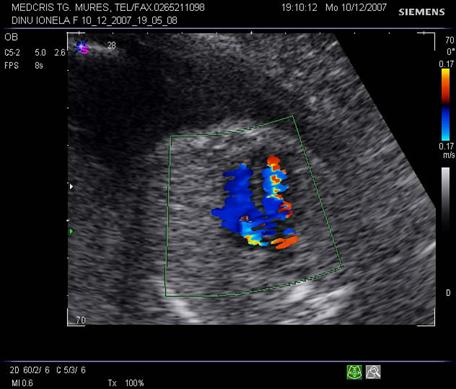

Vasele mari sunt usor de definit ca benzi hipoecogene la imaginea conventionala B mode. Color Doppler evidentiaza si vase mai mici, dar mai ales determina directia fluxului sanguin.[1,8,11]

Fig. nr 183. La examenul Doppler, se poate stabili integritatea septului ventricular, in sectiunea cord in 4 camere